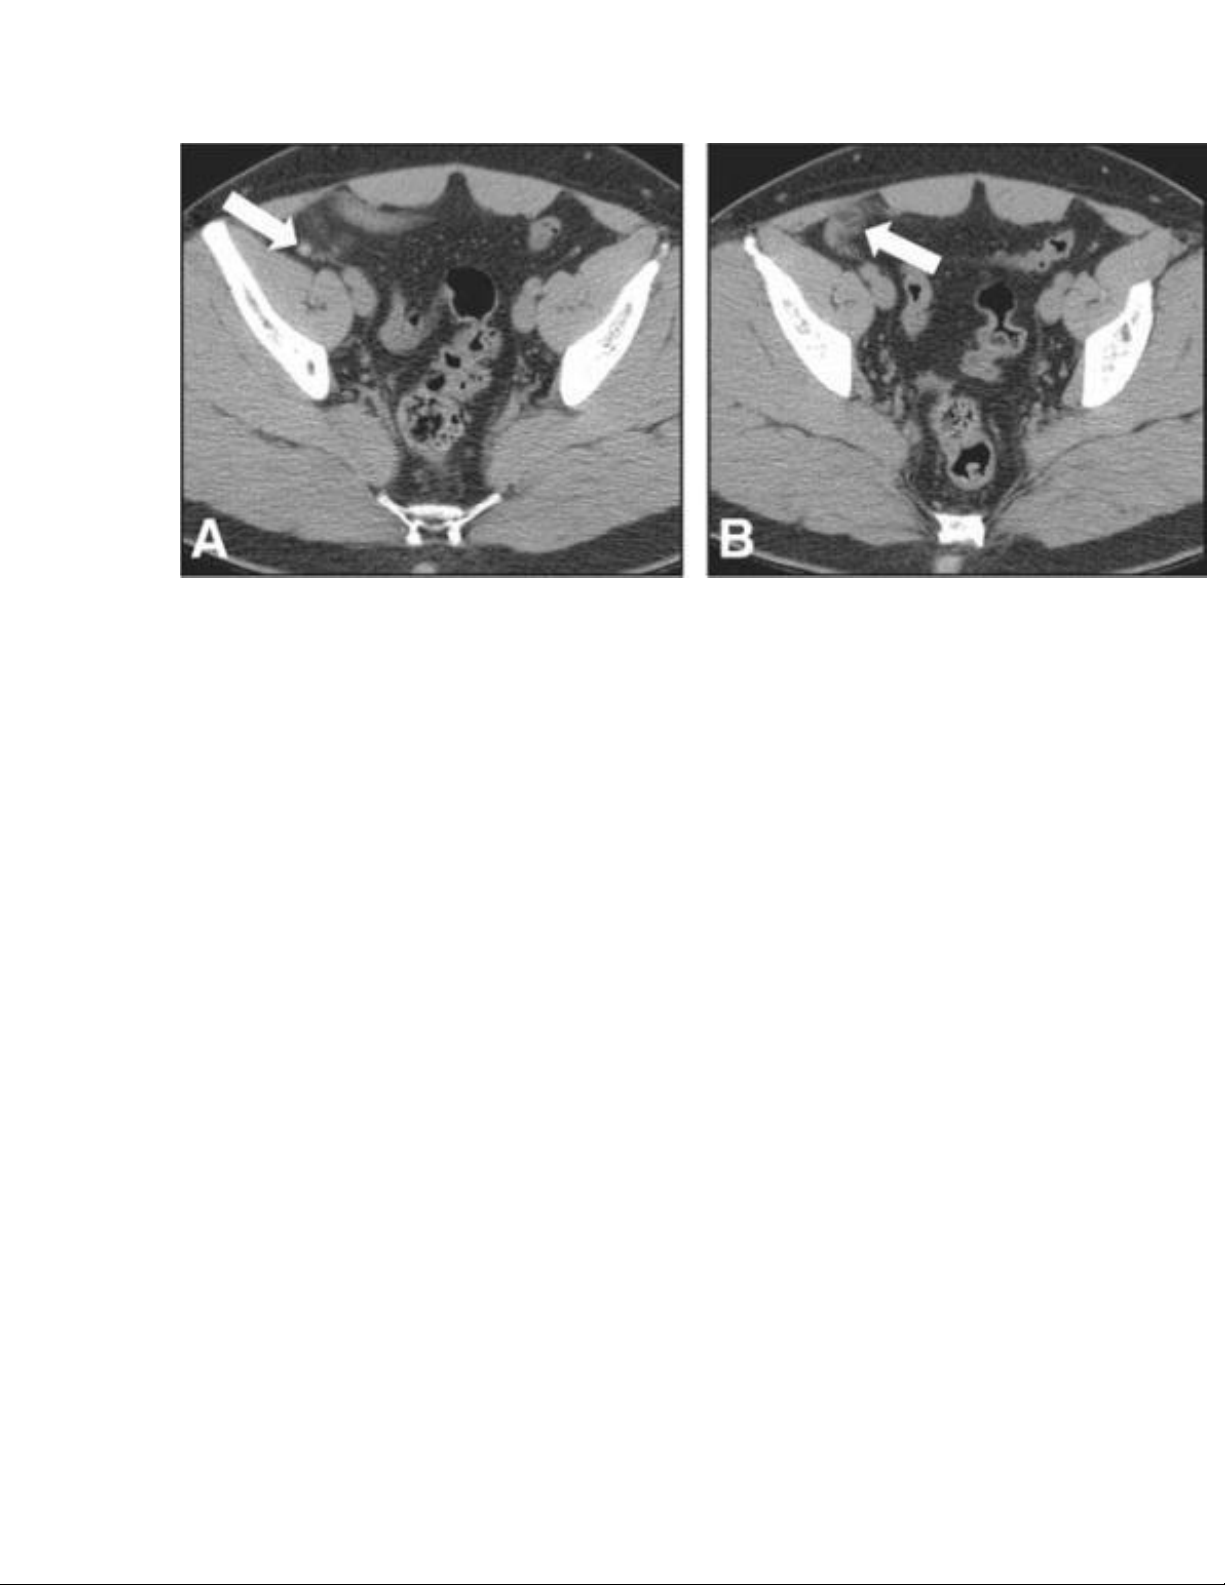

Hình 2. Viêm đỉnh ruột thừa. Nam 23 tuổi đau bụng. A. CT không

cản qaung tĩnh mạch hoặc đường uống thấy ruột thừa bình thường

ở phẩn gần và phần giữa (mũi tên). C, tăng đậm độ mỡ quanh ruột

thừa ở phần xa (mũi tên) phản ảnh viêm đỉnh ruột thừa . Ruột thừa

có đỉnh hoại thư thấy lúc phẫu thuật.